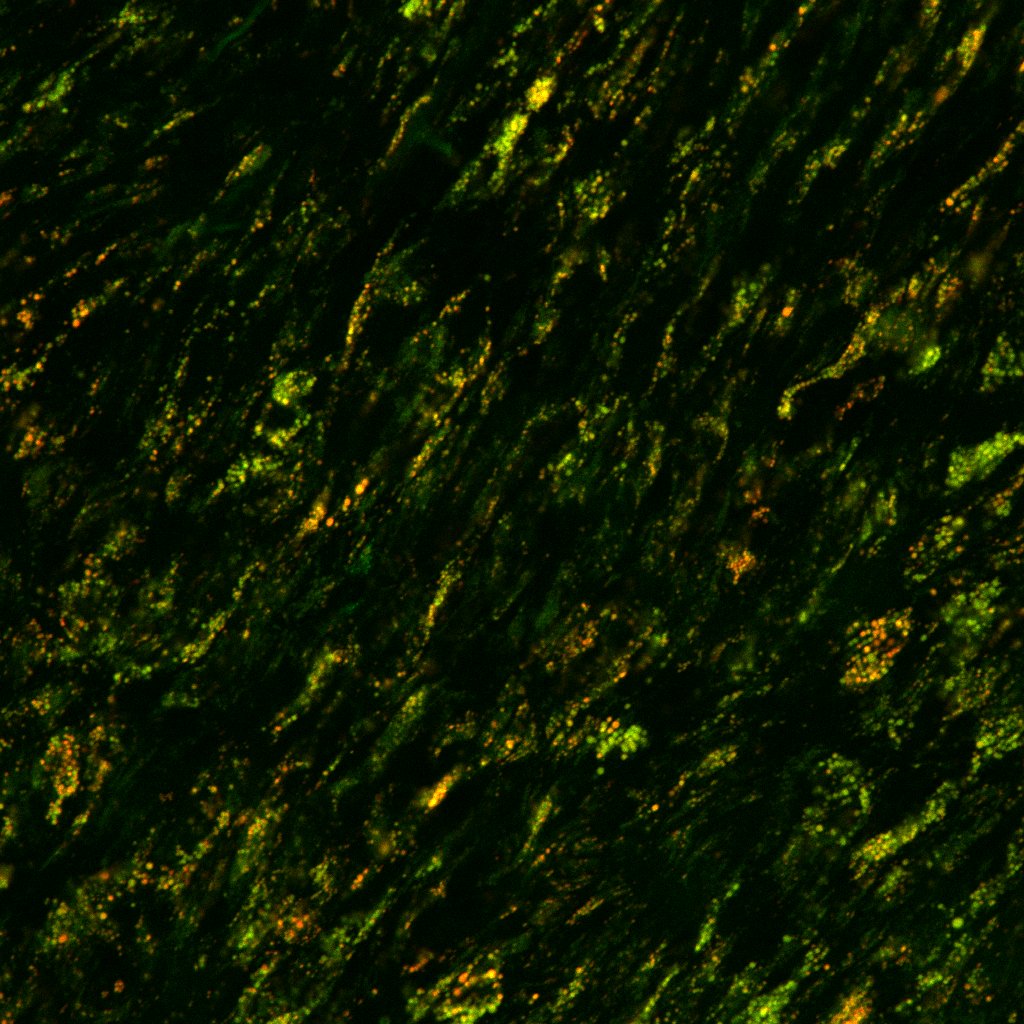

Our study out in print in

@CircRes: Thanks to@Gracedan10_99 &@LabGoldstein at@umichCVC &@UMMicroImmuno Fun pics of#mitochondria in the aorta. We describe a novel pathway on how#aging impairs aortic mito function to accelerate#atherosclerosis: https://www.ahajournals.org/doi/10.1161/CIRCRESAHA.119.315644 …pic.twitter.com/nljsl1e2cI

Excited to share our new study in

@CircRes by@dantyrr@Gracedan10_99 and@LabGoldstein at@umichCVC@UMMicroImmuno@umichmedicine@UMich on how#aging links#inflammation to aortic mitochondrial function to accelerate#atherosclerosis https://doi.org/10.1161/CIRCRESAHA.119.315644 …Hvala. Twitter će to iskoristiti za poboljšanje vaše vremenske crte. PoništiPoništi -